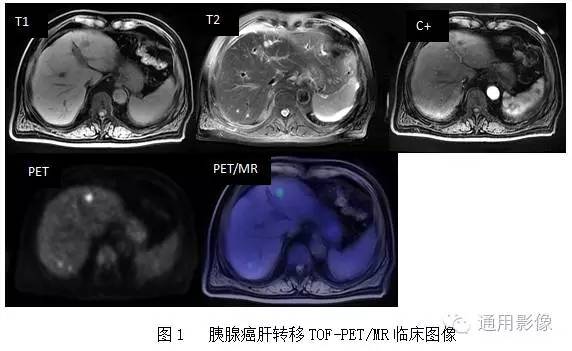

Pet Mr专题 一体化tof Pet Mr腹部占位病变诊断临床应用

MRI(magnetic resonance imaging)検査では撮像 時間が長く,上腹部の検査では,呼吸による動きによ ってモーションアーチファクト(mortion artifact:運 動アーチファクト)が発生し,読影診断に影響を与え てしまうおそれがある.呼吸のような周期的な動きに. 3T MRI が臨床に導入されてから、基本的な撮像技術の重要性がますます高まっている。本講演では、3T MRIにおける躯幹部領域のトピックスである、脂肪抑制、Volume化の流れ、非造影MRAの3点について、GE社MRIの最新アプリケーションと臨床的有用性を中心に紹介する。. く,造影剤が分布した周囲組織のプロトンの緩和を促進(主としてt1短縮効 果)させることにより,t1強調画像で造影効果を発揮する(信号が増強される)。 しかしながら,造影剤濃度が高くなると,t2,t2*短縮効果により信号は逆に 減衰する(図1)2)。.

放射線技師向け kenminkei11. 2.MRIのパルスシーケンス 表在性軟部腫瘍では病変部位や形態が様々で あり,プロトコールを標準化しづらい.当院で 表在性軟部腫瘍の画像診断 391 図1石灰化上皮腫 (a)(b)(c)後背部正中の皮下腫瘤は,MRIのT1強調像,T2強調像でともに低信号で辺縁に. 肝細胞癌はt2強調画像、拡散強調画像で高信号、t 1 強調画像では低信号を呈している。造影ダイナミック検査早期相ではgd.